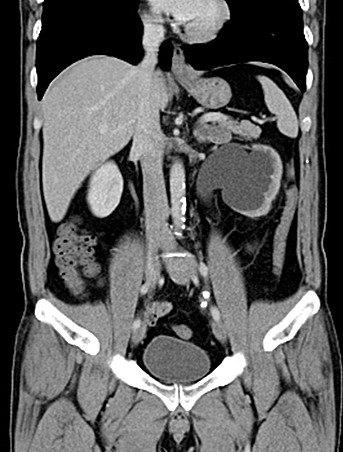

增强CT检查提示:右侧肾脏积水,右肾萎缩,右输尿管下段多发结石

KUB提示右输尿管下段结石呈石街样排列,引起右输尿管完全梗阻,导致右肾萎缩